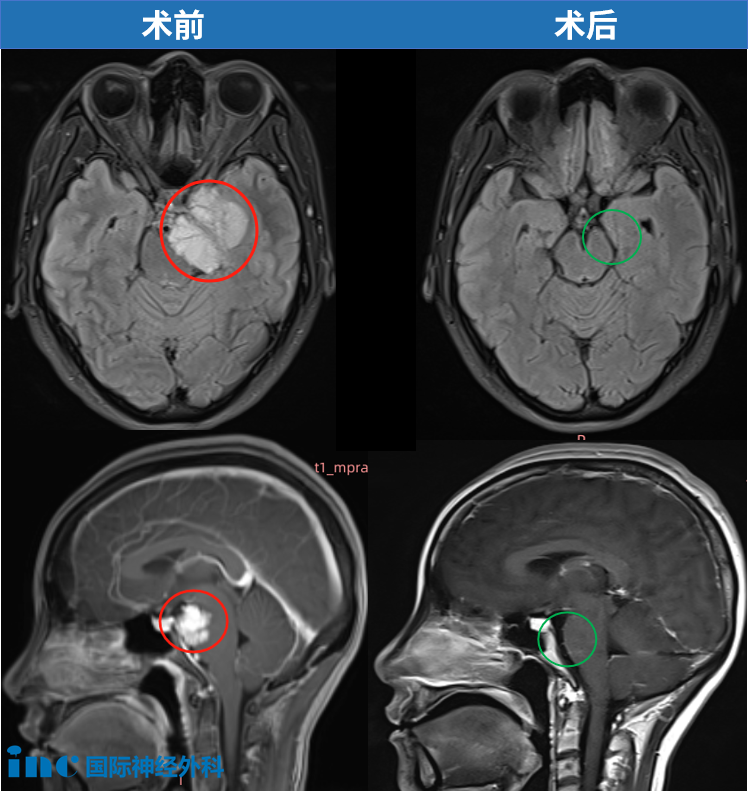

分别在术后 1 周行 CT 及 MRI、2 个月行二次 MRI 复查,结果均提示肿瘤全切除。组织病理学示 WHO I 级。

术后 2 个月 MRI 轴位及矢状位示:脑膜瘤已完全切除,脑干复位良好。